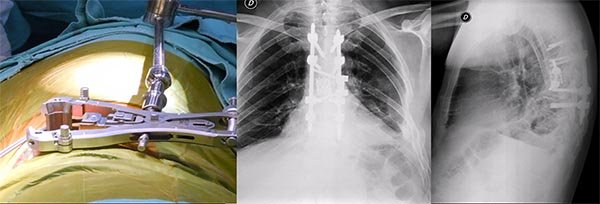

Figura 2:

Caso 24. A y B: Fractura horizontal que compromete cuerpo, pedículo izquierdo y apófisis espinosa de L1 (L1: B1; N1 AOSpine). C y D: Estabilización percutánea T12-L2.

Figura 5:

Caso 8. Se realizó una estabilización percutánea T6-T10. El paciente retornó a UTI, para estabilizar su cuadro respiratorio y hemodinámico.